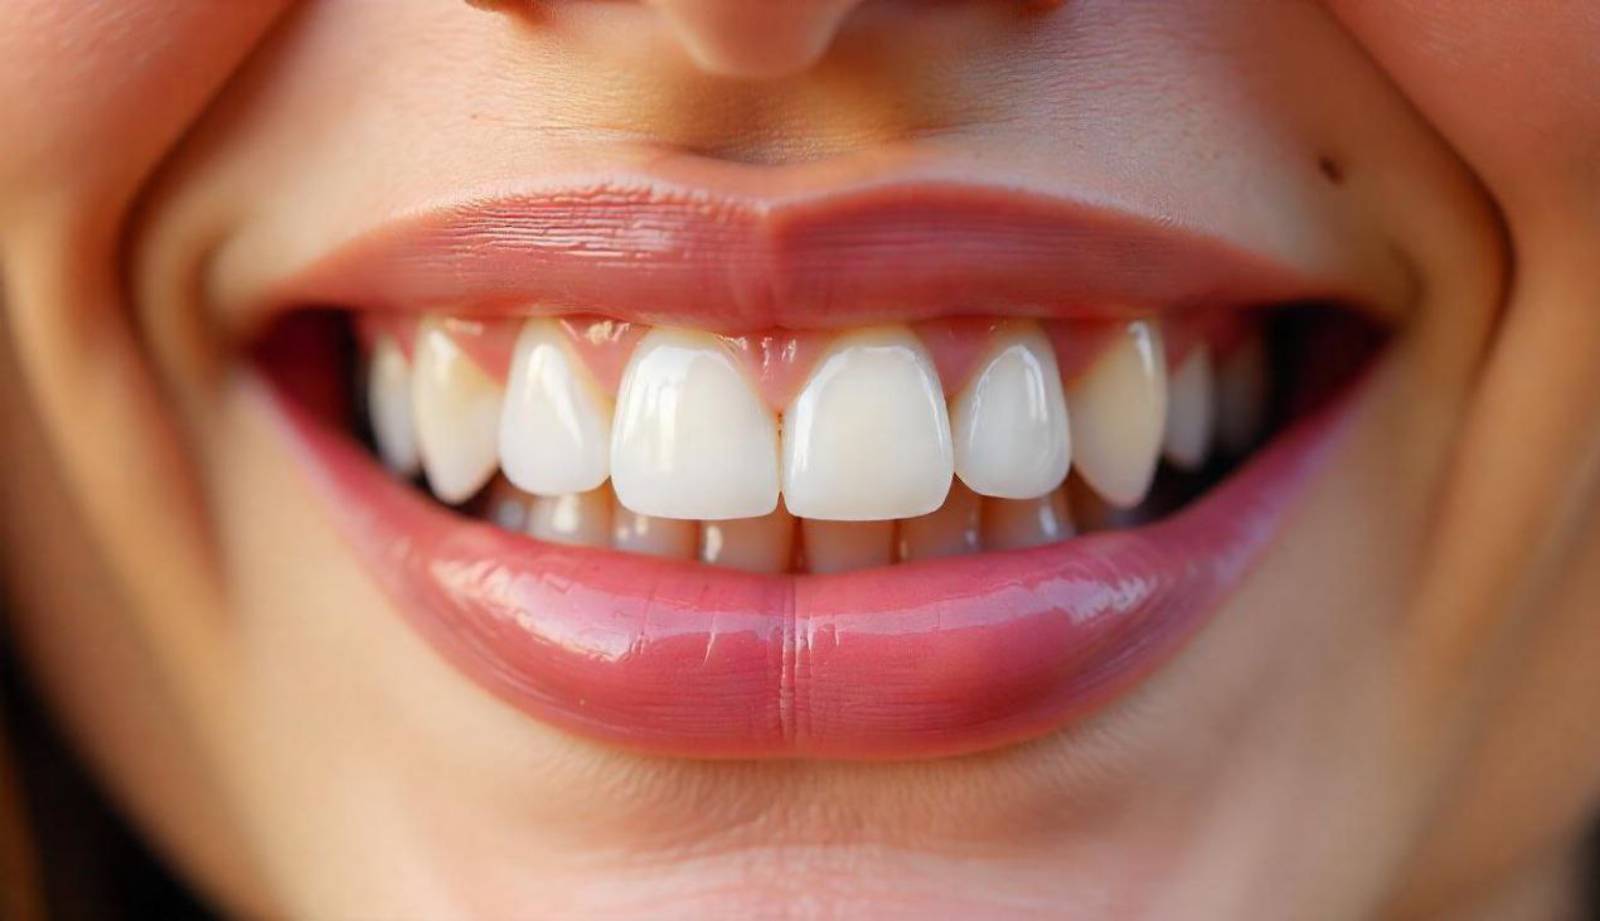

The transformation was remarkable. The reverse curve was corrected, alignment was improved, and the color and contour of the crowns blended perfectly with the surrounding teeth.

The patient was extremely satisfied with the outcome, expressing renewed confidence in their smile and improved comfort while biting and speaking.

Through careful planning and execution of smile design principles, we successfully reversed the unnatural curvature of the upper anterior arch. The result was a balanced, harmonious smile that significantly enhanced the patient's overall appearance.

Outcome: The transformation was not just physical—it had a profound psychological impact on the patient. He reported feeling more confident and happy with his smile for the first time in years. It was a rewarding reminder of the life-changing power of modern dentistry.